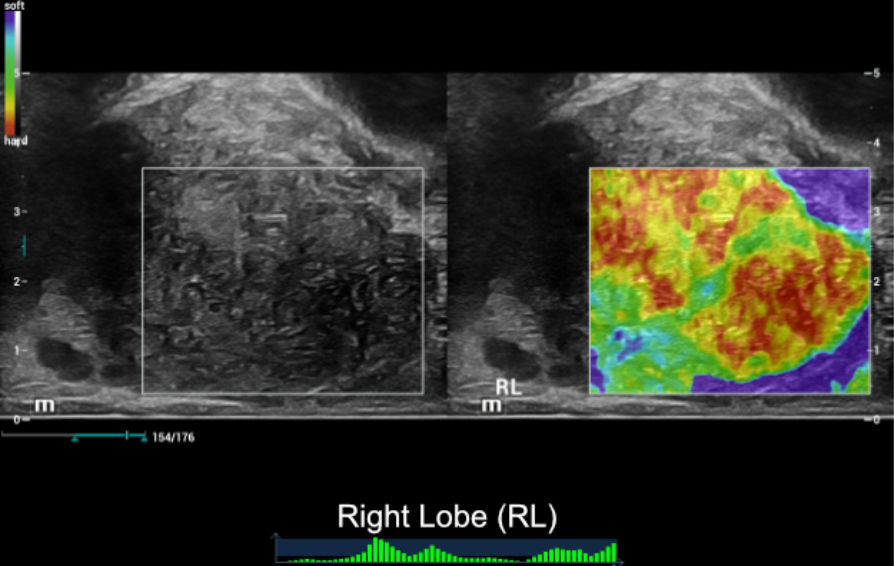

Ultrasound Findings of rigth lobe of the prostate:

NTE ŌĆō Strain Elastography:

SWE ŌĆō Shear Wave Elastography:

- NTE showed a very stiff area which was linked with hypoechoic area in 2D of RL. LL showed typically normal findings with a soft elastogram map and a well-defined border between TZ and PZ.

- SWE showed abnormal stiffness measurements of RL, which mean stiffness value was 34kPa and max stiffness value was 115kPa.

Combined NTE and SWE results, we had more clinical evidence to confidently confirm that this patient had local PCa on RL, and LL of prostate seems to be normal.